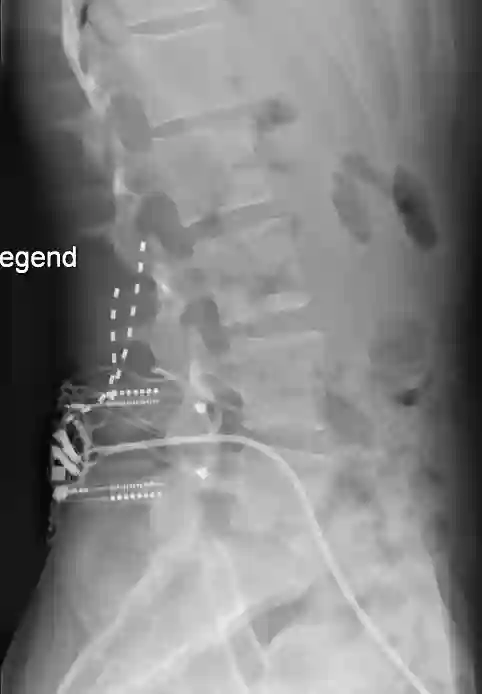

Elektrodendislokation

AP Röntgenbild eines dislozierten SCS Elektrodenpaars.

AP Röntgenbild eines Patienten mit postoperativ dislozierten SCS Elektroden, welche von der BWS auf Höhe LWS disloziert sind.

Laterales Röntgenbild dislozierte SCS Elektroden

Laterales Röntgenbild eines Patienten mit postoperativ dislozierten SCS Elektroden, welche von der BWS auf Höhe LWS disloziert sind.